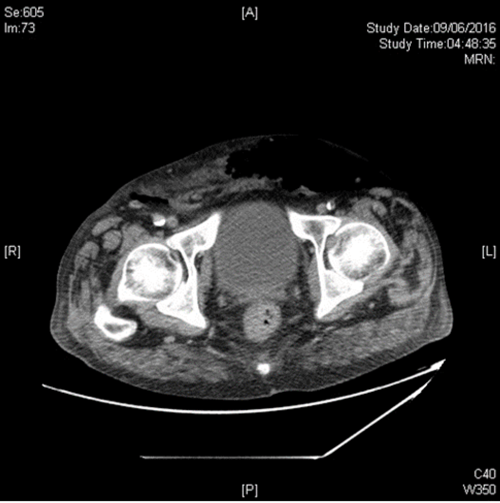

Case 2

A 72-year-old diabetic man presented with acute confusion, tachycardia and pyrexia of 400C after reportedly having had a fall. He was found to be anuric and at the time of catheterisation he was found to have a swollen scrotum with erythema and crepitus extending up onto the perineum, anterior abdominal wall and loin. The posterior aspect of the scrotum was dark purple in colour. Emergency CT detected gas in the retroperitoneum and anterior abdominal wall.

- What is the diagnosis?

- What is the typical microbiology from this condition?

- What is the treatment of choice?

- What is the mortality from this condition?

-

Fournier gangrene, a potentially life-threatening form of necrotising fasciitis involving the male genitalia. It was originally reported by Baurienne in 1764 and by Fournier in 1883 [2].

Wound cultures often yield mixed growth with a combination of aerobic (e.g. E. coli, klebsiella, enterococci) and anaerobic organisms (bacteroides, clostridium, microaerophilic streptococci).

Prompt diagnosis is critical because of the rapidity with which the condition progresses. Immediate debridement is essential, with extension excision of all infected tissue until normal fascial planes are found. This may extend up into the abdomen or into the perineum, as in this case. Orchidectomy is almost never necessary because the testis have their own blood supply and do not usually get involved by the infective process. If the urethra is suspected to be involved a suprapubic catheter should be inserted. This should be combined with aggressive resuscitation and broad spectrum antibiotic cover in advance of the surgical debridement [2].

The mortality rate averages approximately 20% [2].